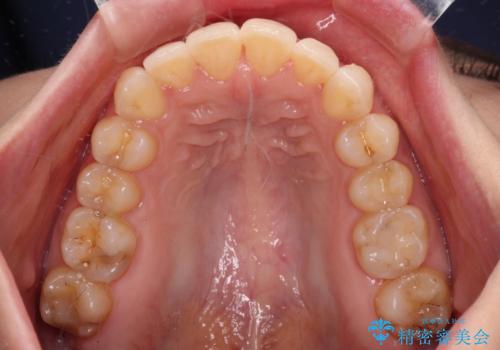

- 上下の前歯のデコボコを気にして来院された患者様です。

妊娠中であり、途中通院が難しくなる可能性があることから、インビザラインによる矯正治療を行うこととしました。

上下顎歯列全体の後方移動とIPR(歯と歯の間を削る)によってデコボコが解消するように設計しました。